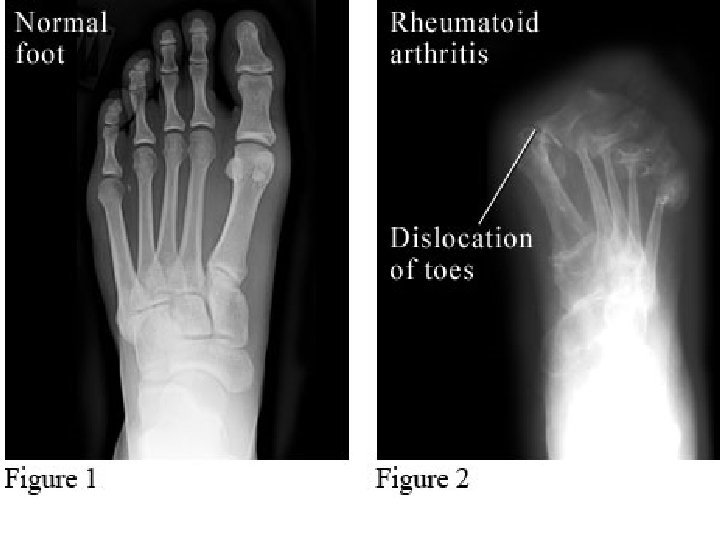

Symmetric peripheral polyarthritis: • 3 or more Joints for >6 weeks • Small Joints – Hands & feets – Peripheral to Proximal • Leads to deformity & destruction of Joints.

4. Radiology: • Evaluate disease activity & joint damage. a. Plain Films. b. Color Doppler U/S & MRI

Severe case • >20 persistently inflamed joints • Rapid decline in functional capacity • Radiographic evidence of rapid progression of bony erosions & loss of cartilage • Extra-articular manifestations.